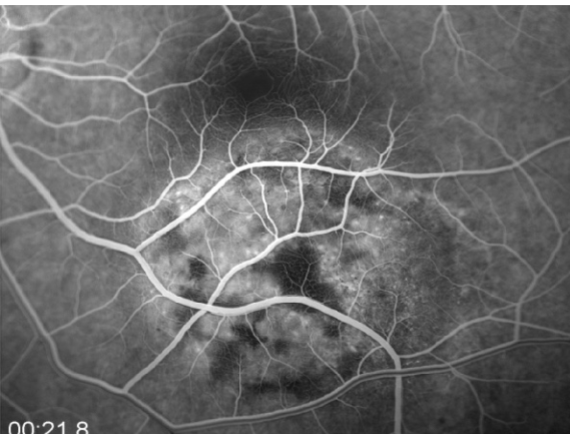

IVFA

mottled fluorescence in arteriovenous phase, progressive staining, prolonged dye retention, double circulation

what does a choroidal melanoma show on IVFA?

choroidal melanoma

melanoma

melanoma

melanoma

melanoma

melanoma

melanoma

melanoma

melanoma

melanoma

melanoma

melanoma

melanoma

melanoma

melanoma

melanoma

melanoma